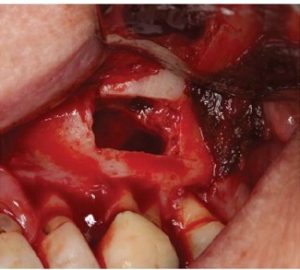

A chisel was used to elevate the cortical plate and root resection performed with Lindemann burs (Figure l0).

The cortical window was placed in sterile saline while the endodontic microsurgery was completed. After resection

using Lindemann burs, the root periphery was stained with methylene blue and examined for anomalies and the root canal space was retro-prepared with ultrasonic tips to a depth of three millimetres, creating a reservoir for the retro sealing materials.

The retro-preparation was rinsed with ethylenediaminetetraacetic acid (EDTA) and dried with paper points.